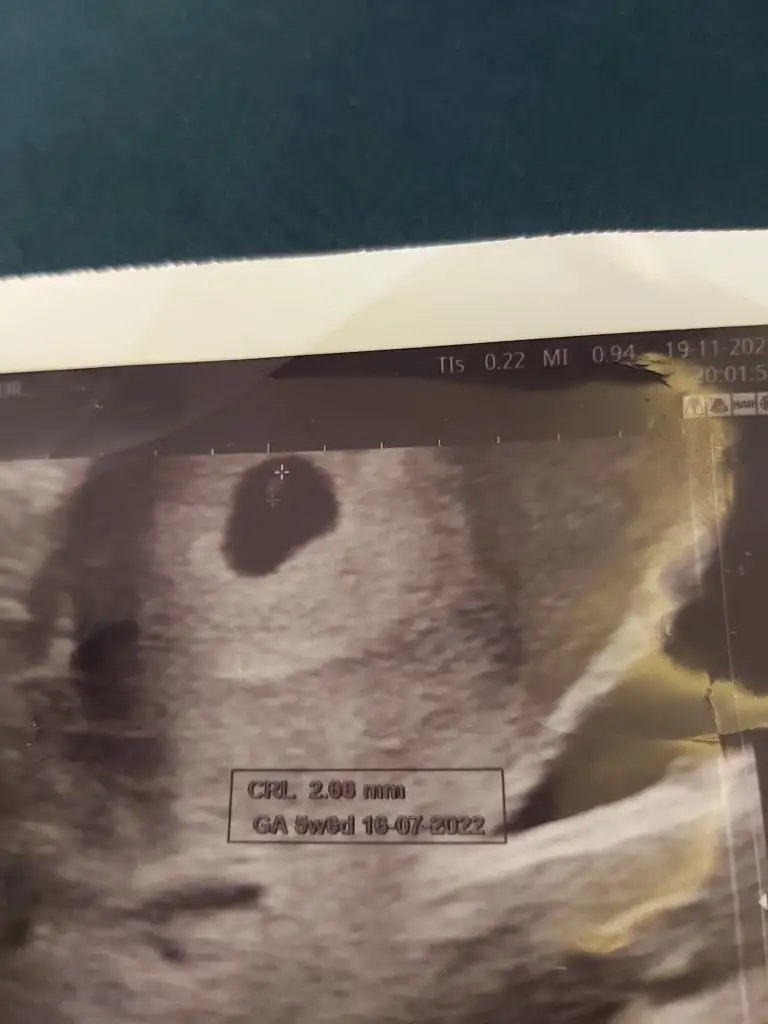

Canim benim 7. Haftamda var ilk ultrasonum yolluyorum sana5+6 yani 6.haftamdaki usg’de belli oldu teori, senin de varsa 6-7.haftaya kadar bakalım beraber tutacak mı

5+6 yani 6.haftamdaki usg’de belli oldu teori, senin de varsa 6-7.haftaya kadar bakalım beraber tutacak mı

Sanki sola daha yakın gibi canım, erkek gibi yani ne dersinCanim benim 7. Haftamda var ilk ultrasonum yolluyorum sana

Canim kesenin içinde nereye yakin oldugu onemli degil mi bu teoride ? Burada solda duruyor bence deSanki sola daha yakın gibi canım, erkek gibi yani ne dersin

Evet canım, kesede sola daha yakın geldi bana da, ve karındansa erkek demekmiş ya..Canim kesenin içinde nereye yakin oldugu onemli degil mi bu teoride ? Burada solda duruyor bence de